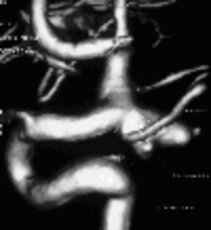

Left: Angiographic view of an aneurysm

Right: Three-dimensional illustration of the same aneurysm